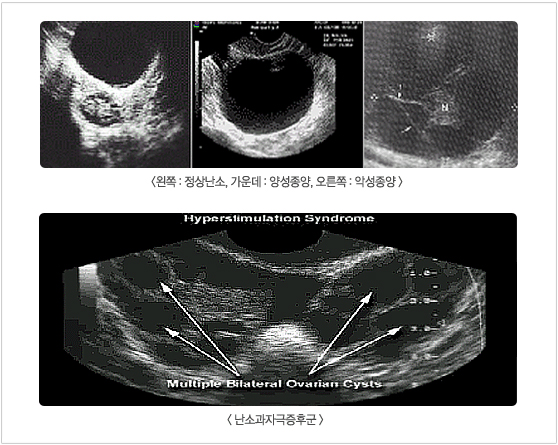

난소암은 침묵의 살인자 라고 표현하고 싶다. 청주에서 진료를하고 내손에서 난소암으로 진단받은 환자가 10명쯤 된다 난소암의 발생빈도는 미국은 일년에 26700명 이새로 생기고 그중에서 2/1정도가 병에걸려서 죽게된다 산부인과의 악성종양 중에서 가장 치사율이 높고 진단시 3/2에서 초기 발견시 에 전이 돼있다. 우리나라는 년내에 750명이 새로 생긴다 과거에는 산부인과 의사는 손끝에 안경이 달려있는 것처럼 질내로 의사의 둘째넷째 손가락을 집어넣고 배를 만져서 모든 질환을 진단했다. 그러나 초음파의 발달로 질초음파(연필 4개를 합쳐놓은 정도의 두께의 봉이)로 전혀 통증이 없이 난소를 정확하게 그릴수 있다. 질속으로 들어간 초음파는 마치 내시경을 본듯하게 배속의 여성 생식기를 그릴수 있다.

난소는 독특한 장기로 여러 종류의 종양이 생길 수 있으며, 다른 장기에서 발생한 여러 종류의 암들이 난소로 전이될 수 있습니다. 난소암은 선진국에서 발생 빈도가 높으면 최근 들어 우리나라에서도 증가 추세에 있습니다. 난소암의 대표적인 상피성 난소암은 여성 생식기에 생기는 암 중에서도 가장 예후가 나쁘며 발견 후 5년간 생존할 확률이 약 25%정도 밖에 되지 않습니다. 난소암은 전 연령층에서 생길 수 있으나 대부분 40-70세에서 발생하며 주로 50대 여성에서 호발합니다.

난소암의 발생과 관련된 위험인자는 아직 확인된 것이 거의 없으나 어머니나 자매중에 난소암 환자가 있는 경우, 임신 경험이 없는 경우에 발생 빈도가 높은 것으로 알려지고 있습니다. 난소암의 조기 진단은 자궁 경부암이나 자궁 내막암에 비하여 상당히 어렵습니다. 정기적인 부인과 진찰, 초음파 검사, 혈액 검사 등이 조기진단에 도움을 주고 있으나 초기의 암을 발견하는 것은 아직도 한계가 있습니다. 초음파 검사상 난소에 지속적으로 종양이 발견되거나, 40대 특히 폐경기 이후에 난소에 종양이 있는 경우는 복강경 검사를 이용한 조직 검사를 시행하는 것이 도움을 줍니다.

난소암 관련 영상

난소암 관련 영상